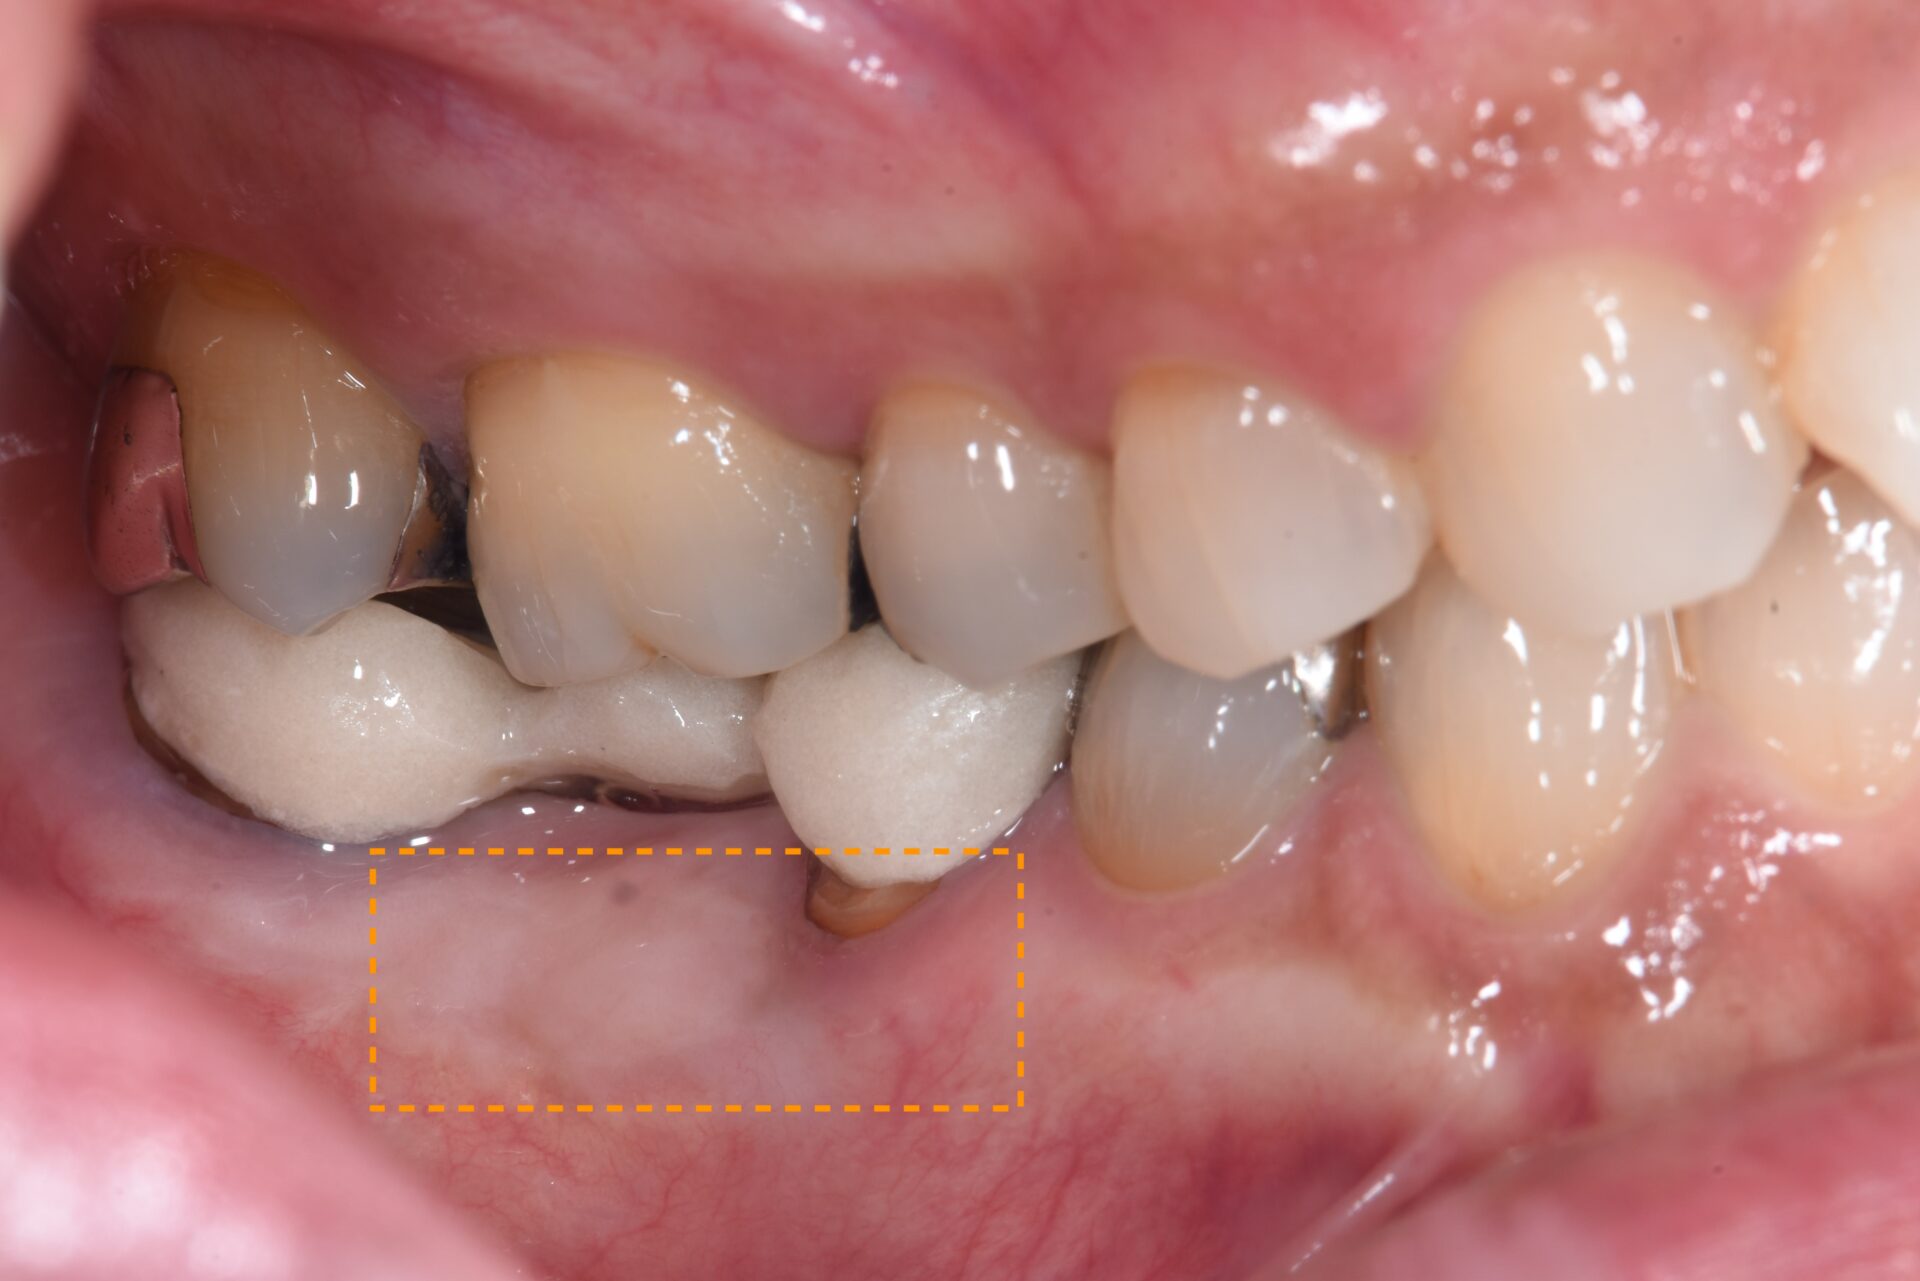

FGG(遊離歯肉移植術) 臨床例①

患者さんは、左下奥歯の周囲に付着歯肉が不足しており、ブラッシングの際に痛みがあり清掃が難しく、炎症を繰り返していました。歯肉が薄く柔らかいため、長期的な安定には不安があり、遊離歯肉移植術(FGG) を行うこととしました。

術後1ヶ月